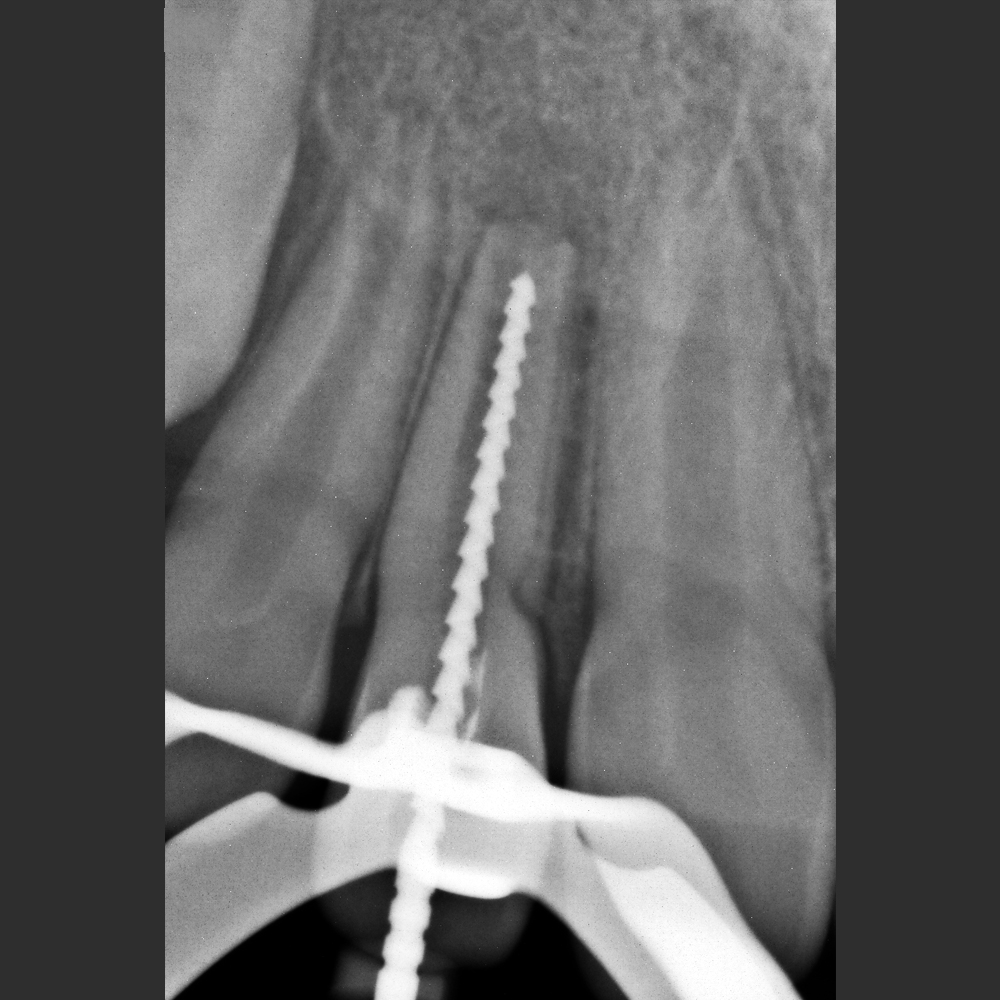

New IDA –Tamaño 2 (área activa: 26x36 mm)

New IDA son los sensores intraorales de la linea New Ida con soluciones eficientes de las imágenes para un diagnóstico nítido, preciso y seguro.

Captura imágenes de alta definición en tiempo real.